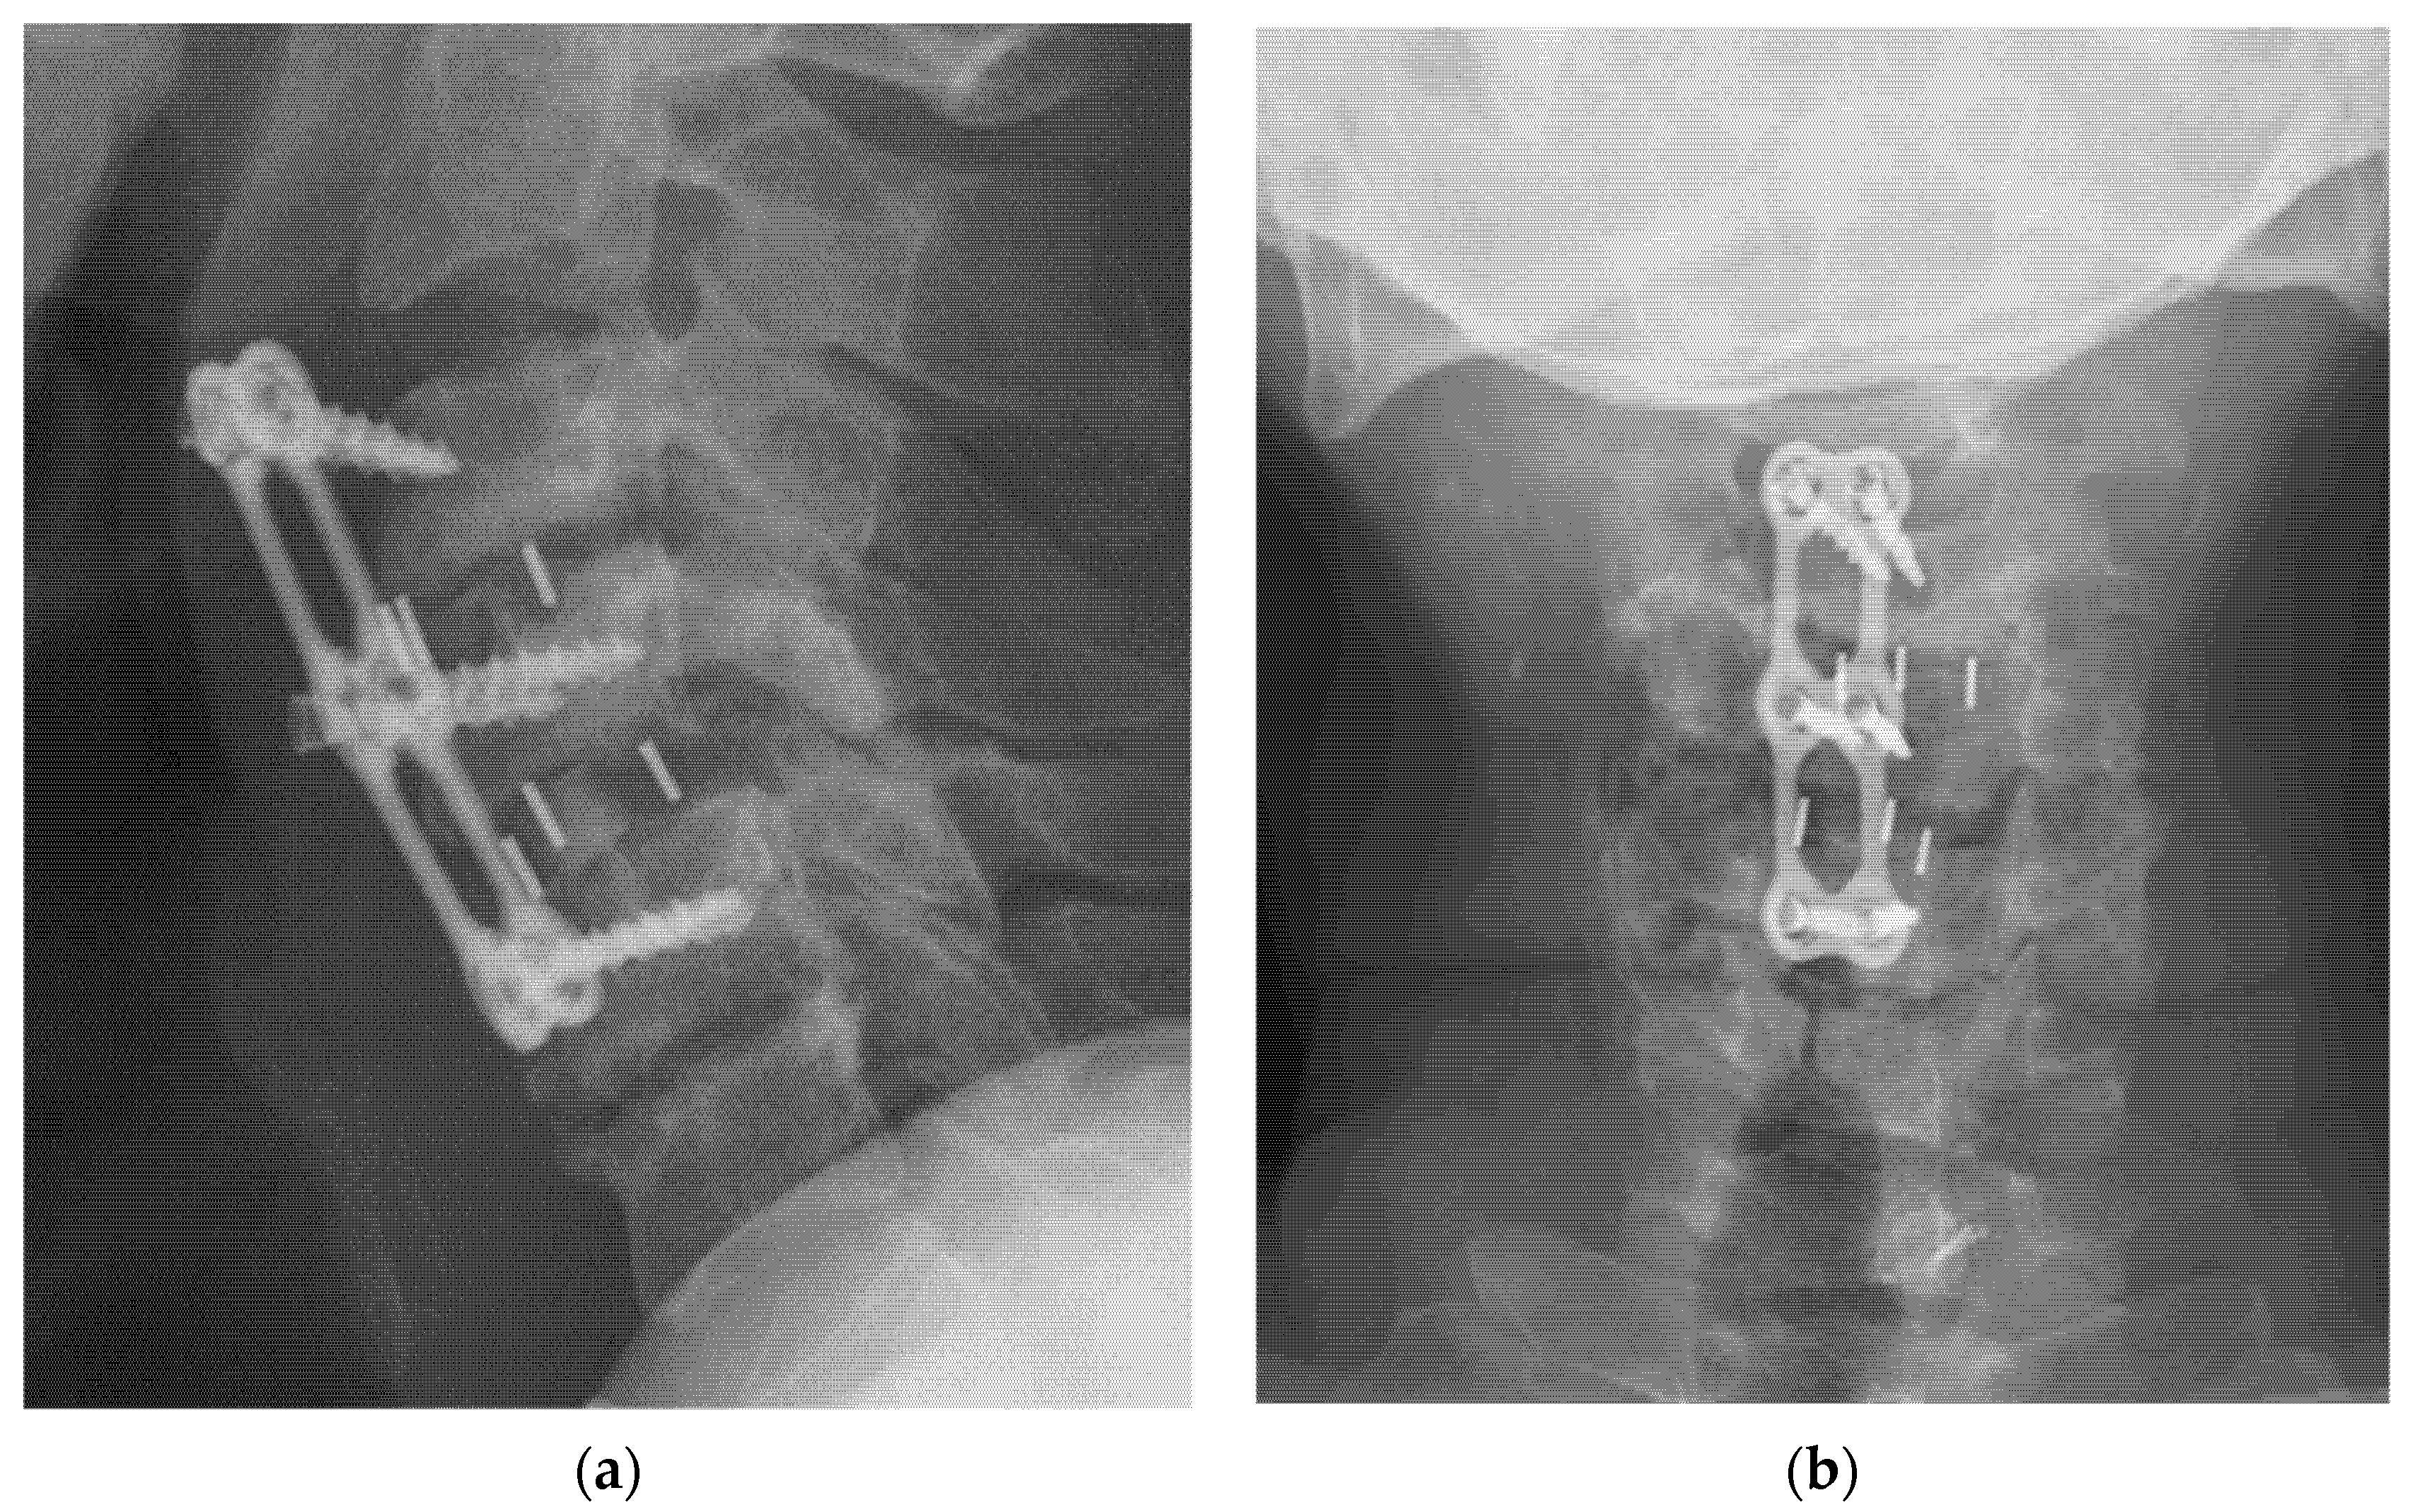

2.2. Surgical Methods

2.3. Laboratory Profiles and Radiographic Assessment